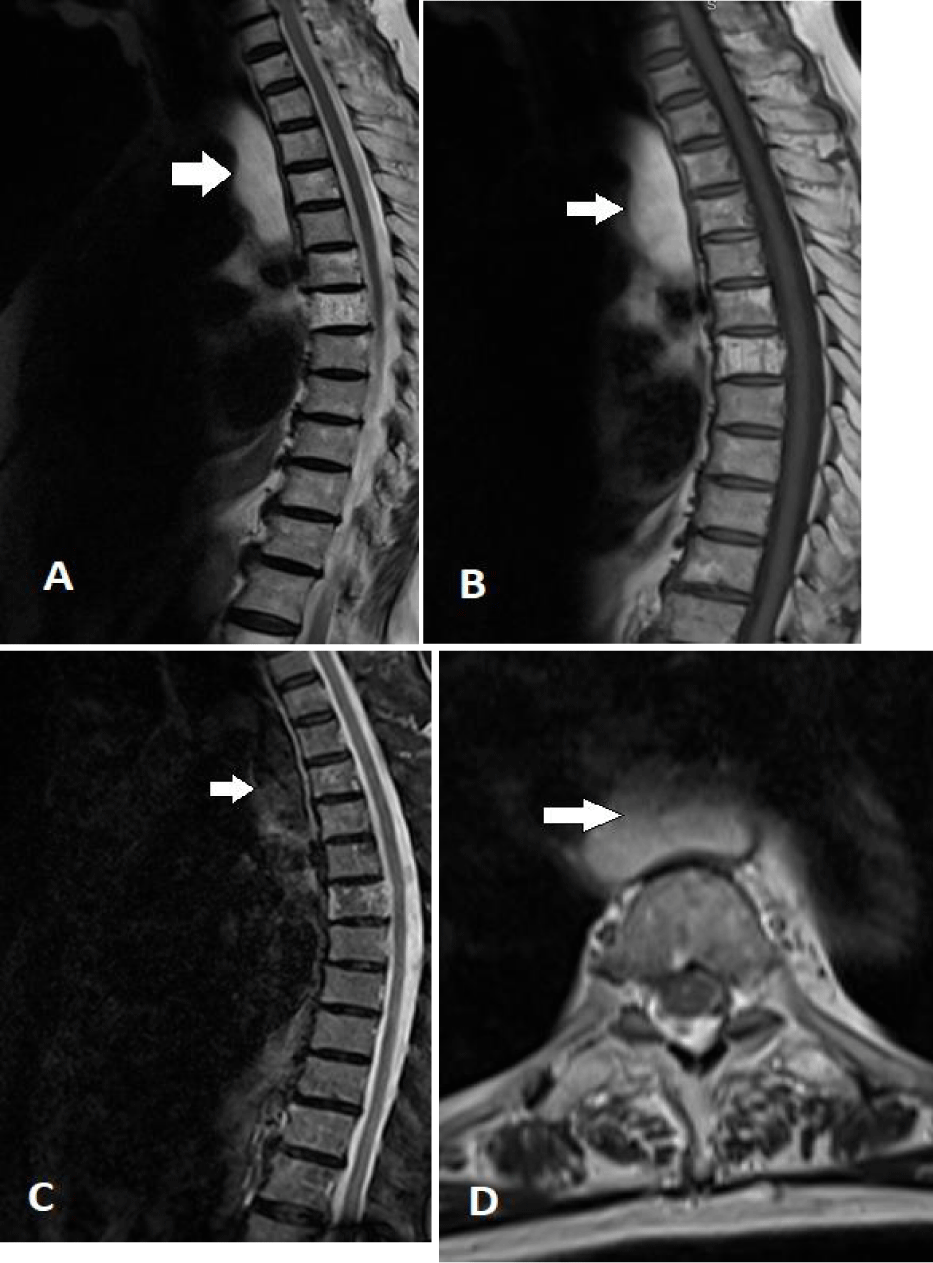

The mass was partially seen in an older MRI of the thoracic spine done 12 months prior to the CT scan, but not reported/documented (Figure 3). The family clinic then referred the patient to the GI clinic for further evaluation and upper GI endoscopy.

Accurate diagnosis requires a comprehensive examination, imaging techniques (such as barium swallow, CT chest, and MRI), and upper GI endoscopy [8]. On a CT scan, lipomas appear as homogeneous fat-density lesions (-40 to -120 HU) [9]. MRI reveals lipomas as T1-weighted hyperintense areas that become hypointense on fat-suppressed images [10]. Conversely, liposarcomas are heterogeneous with high signal intensity on T1 and T2-weighted images [11]. Taylor AJ, et al. [5] noted that strands within a homogeneous fatty tumour may be due to inflammatory changes and should not be mistaken for liposarcoma, a rare occurrence.